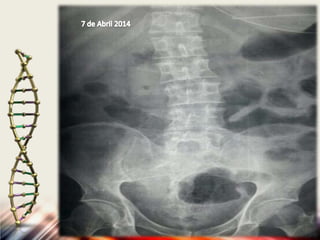

7 de Abril del 2014 hora:00:00 hrs

7 Abril del 2014